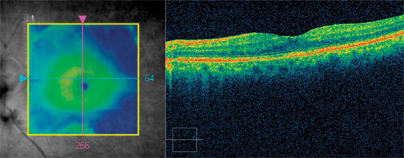

As part of the patient's clinical evaluation, baseline color photographs and a fluorescein angiogram were obtained. The fluorescein angiogram revealed moderate macular edema with diffuse leakage and staining on the optic nerve head. I believed the patient had mild DME with probable postoperative cystoid macular edema (CME) superimposed on his condition. Cirrus HD-OCT documented the precise location and the extent of the CME (425 microns), although it didn't show any evidence of a taut posterior hyaloid or other vitreomacular abnormalities (Figure 1).

Figure 1. These images from Cirrus HD-OCT show extensive macular edema post cataract surgery centrally as well as temporally to the fovea.